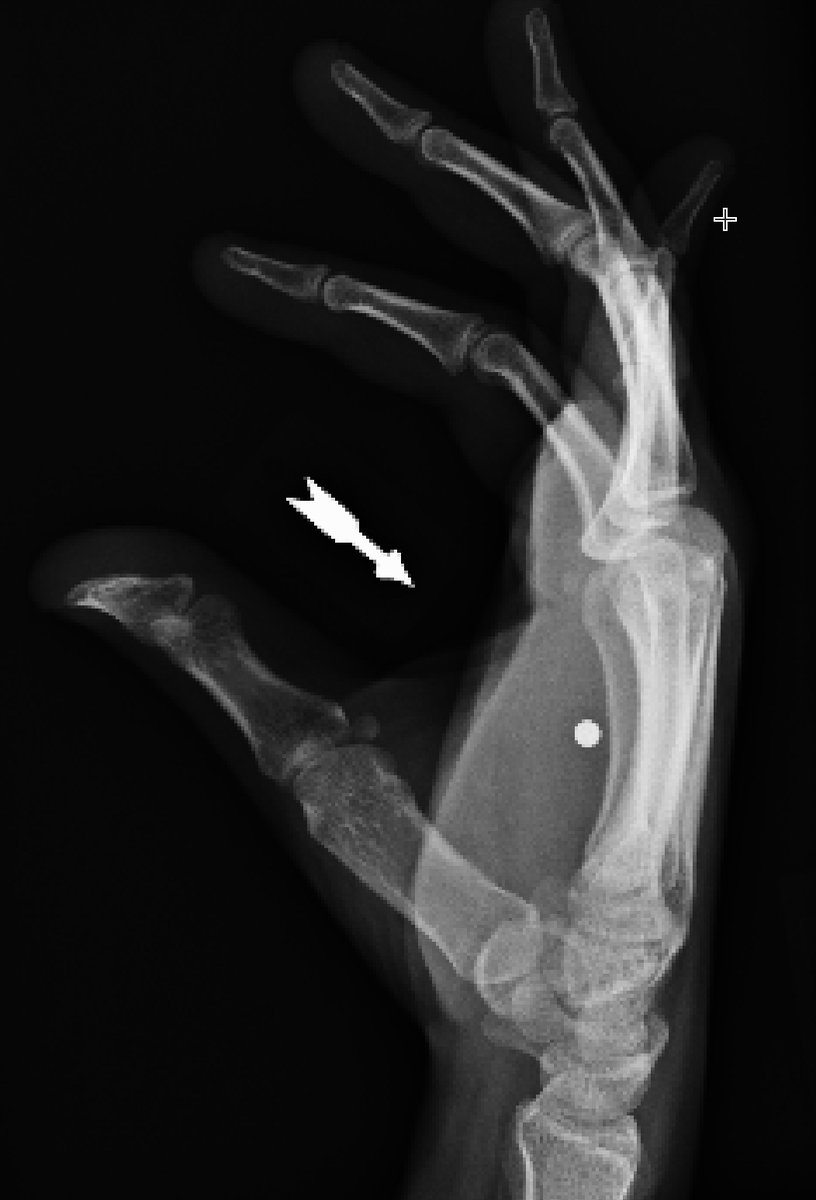

Acute BB gun injury with retained pellet to hand

Piece of glass at MCP jt after closed fist injury with window 1 day ago. Note movement of FB with flexion. Glass attached to extensor tendon.